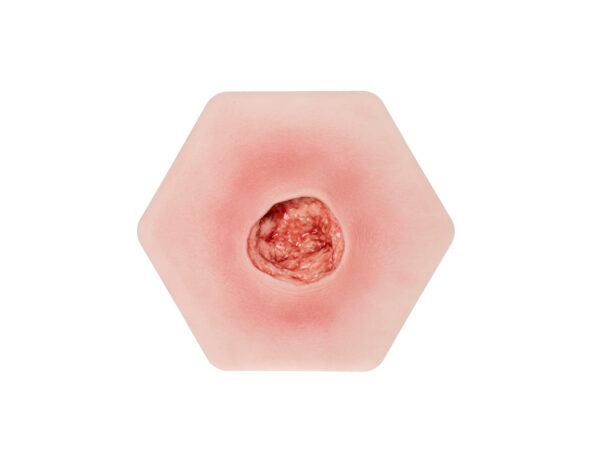

| 상처 유형 |

Amputation, 욕창, 수술 상처, 궤양, 미확정 |

MEDICAL FX Germany의 “Base Model 6개의 상처가 있는 두 발가락 발”은 두 개의 남은 발가락과 6가지 다른 상처 유형이 있는 발의 상세한 표현을 제시합니다. 4가지 피부톤으로 제공됩니다. 선택적으로 깨끗한 상처 또는 영구 부착된 상처 코팅으로 제공됩니다.